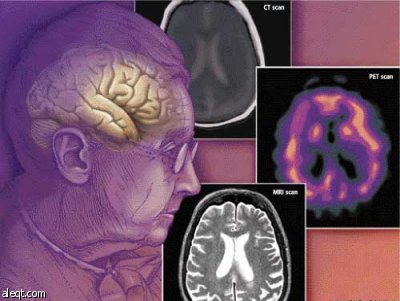

أظهرت نتيجة أبحاث أن الأجزاء الدماغية التي تتلف بسبب مرض باركنسون ومرض الخرف تزيد طبقاً لتحرك البروتين المعدل بين الخلايا العصبية مثل مرض جنون البقر.

وأوضح الأستاذ لي سيونغ جيه في قسم العلوم الحيوية الطبية في جامعة كونكوك من خلال بحث مشترك مع الأستاذة لي هيه جين في قسم العلوم الطبية في جامعة كونكوك والأستاذة إيليزر ماسلياه في جامعة كاليفورنيا ، أنه كشف للمرة الأولى في العالم النقاب عن الحقيقة التي تشير إلى أن الأمراض الدماغية التي تبدأ في جزء دماغي تتسع لتعم مختلف الأجزاء الدماغية طبقاً لتحرك اللبروتين المعدل بين الخلايا العصبية.

ويعتبر هذا البحث انجاز كبير أشار إلى وجود تشابه في سريان الأمراض الدماغية مثل مرض باركنسون، ومرض الخرف ومرض جنون البقر في داخل الجسم ، و نموذج جديد خاص بمبدأ سريان الأمراض الدماغية.

على وجه الخصوص، اقتصر انتشار وسريان الأمراض الناتجة عن البروتين المعدل على بعض الأمراض مثل مرض جنون البقر إلا أن هذا البحث قدم دليلا تجريبيا لتطبيق مبدأ هذا الانتشار على نطاق واسع من الأمراض الدماغية المتأزمة.